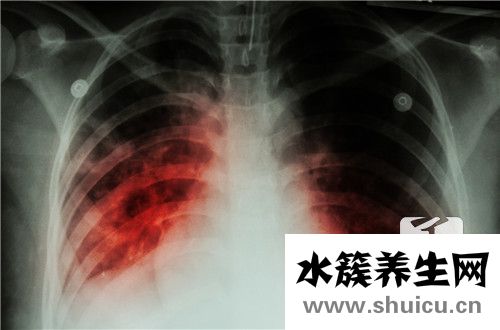

如果肺動脈的工作壓力過高,會導致體內右心衰竭,患病率也很高。 如果不及時治療立即,很容易導致患者死亡和致殘,因此每個人一定都應該做好治療。為預防疾病,過度的肺部工作壓力癥狀包括呼吸不良和疲勞 ...